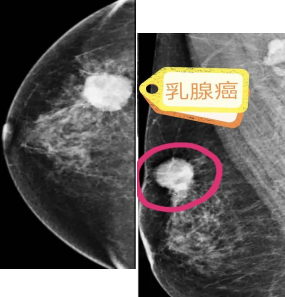

早期乳腺癌的“照妖镜”

临城县中医医院开展数字化乳腺钼靶检查项目,具有全面、直观、重复性好、操作简单、安全和费用比较低廉等特点,对于临床不可扪及肿物的或者以微小钙化簇为唯一表现的早期乳腺癌具有特征性的诊断意义,被誉为国际乳腺疾病检查的“金标准”,优点还包括可以检出85-90%的50岁以上患者的乳腺癌;可以有效降低乳腺癌死亡率;可以检测出微小钙化。